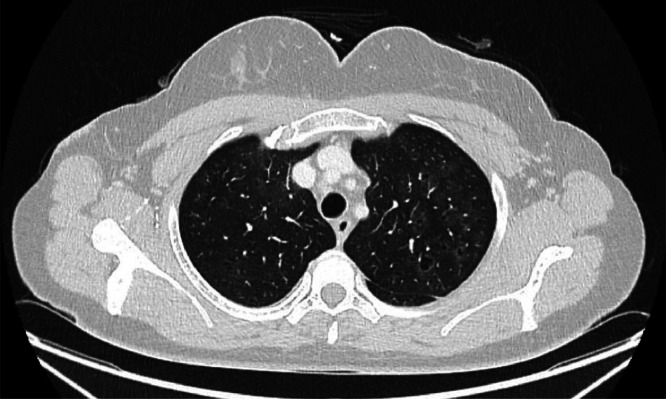

Results: Radiological evidence of RB-ILD was identified and a bronchoscopic lavage demonstrated the presence of striking green pigmented macrophages, presumed to be chlorophyll uptake.

Abstract Image